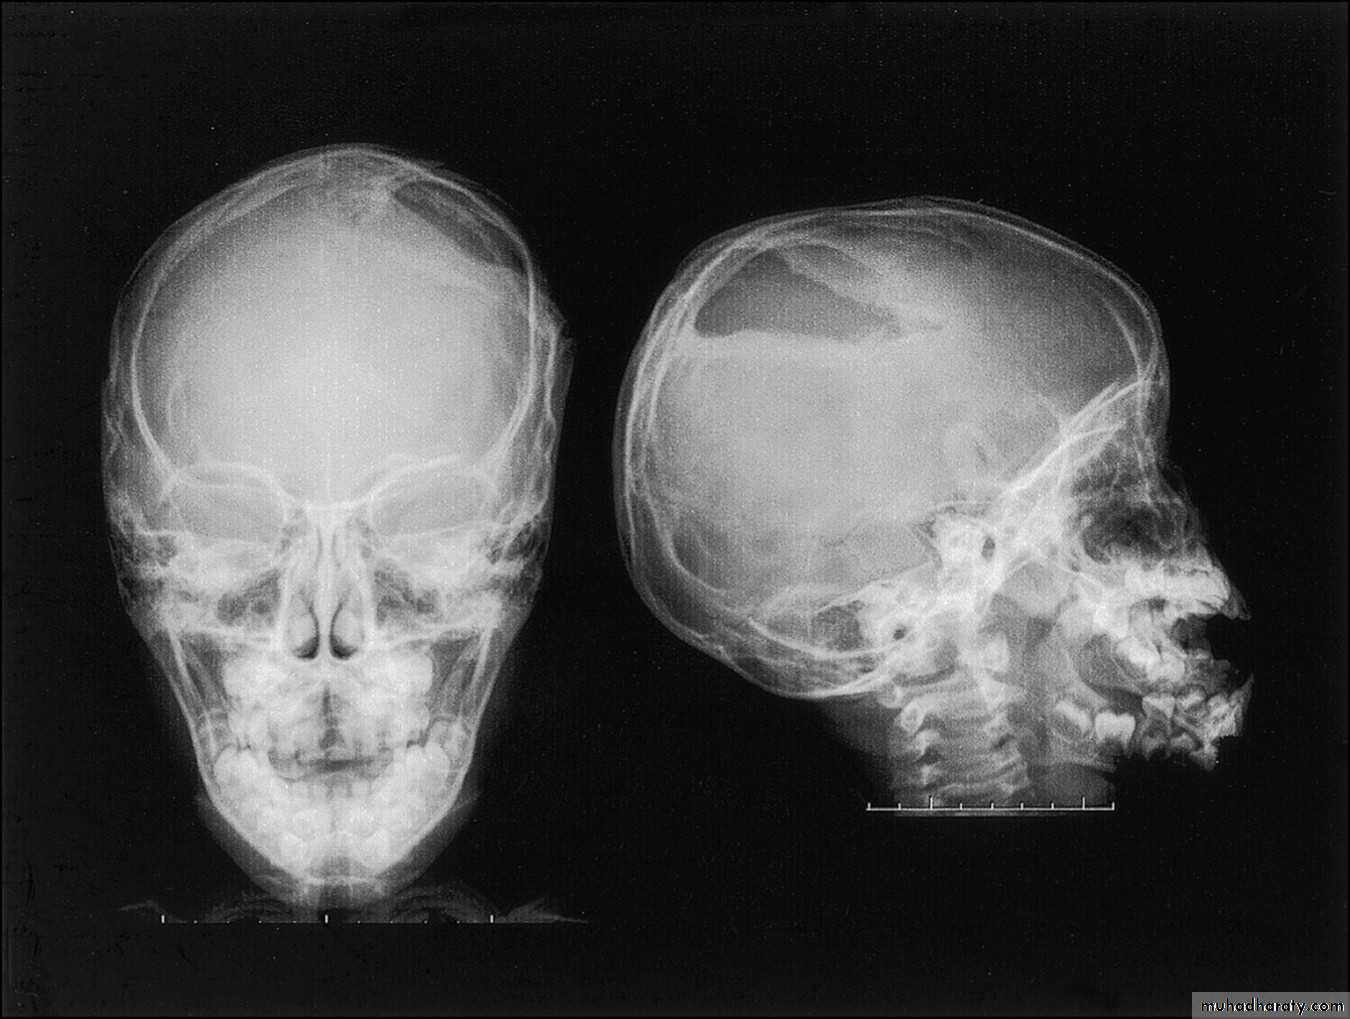

Linear Fracture Compound depressed Fracture

Sometimes just by inspection we can see the brain tissue out, or by palpation we can feel the depressed segment, but sometimes the inner table is the, only depressed part (inner table is the inner side of the skull bone), so the X-ray is the most essential and diagnostic procedure (and this may be the only case in which the skull X-ray is very essential for diagnosis).Surgical management: